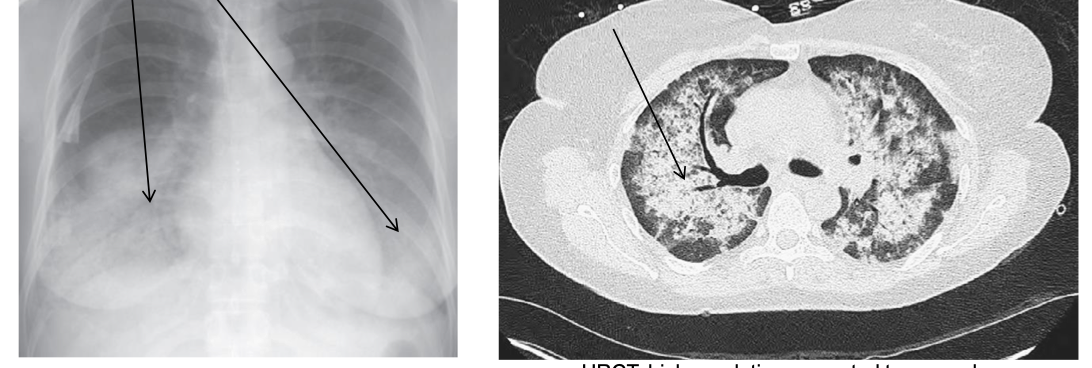

what type of AAV would this person be struggling with?

MPA: more frequently associated with alveolitis and pulmonary hemorrhage than GPA

GPA. GPA is more frequently associated with pulmonary nodules than is MPA